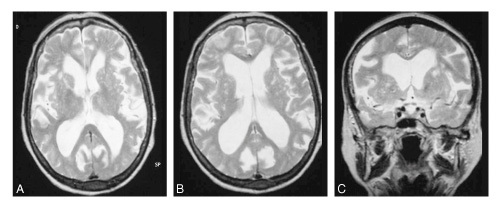

Un patient présente une marche à petit pas, avec anomalie des réflexes posturaux et une ataxie. Une IRM séquence T2: est réalisée: quel diagnostic?

multiples lacunes des noyaux gris centraux car multiples hypersignaux T2

(état lacunaire)